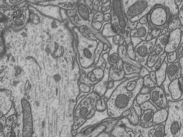

Refer to caption

(a) EM image

(b) Pixel-wise annotation

(c) Point annotation

(d) Bounding-box annotation

Figure 10: An illustration of pixel-wise annotation, point annotation and bounding-box annotation for mitochondria segmentation from electron microscopy (EM) images.